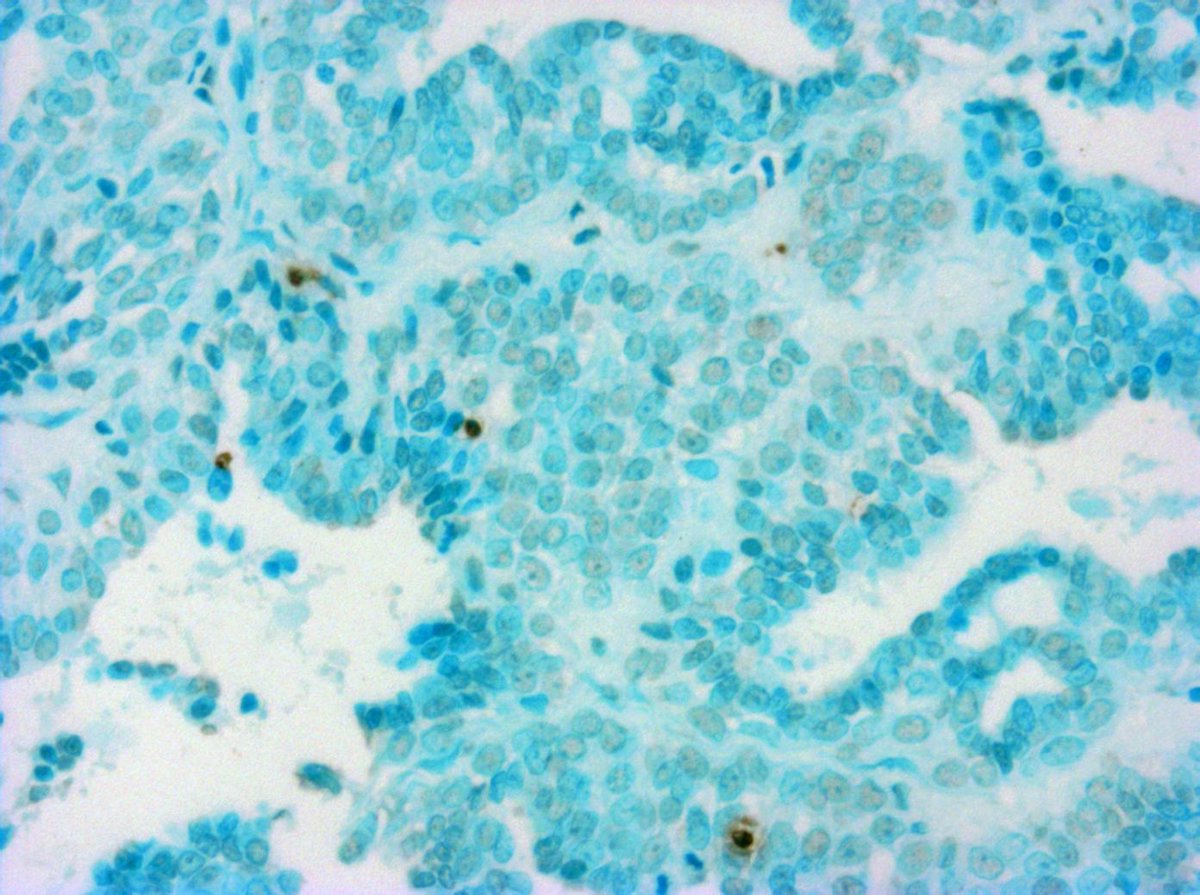

Células de un tumor de mama

Investigadores del Instituto para la Formación e Investigación 'Marqués de Valdecilla' (IFIMAV) han colaborado en un estudio sobre el efectos del docetaxel en los casos de cáncer de mama de alto riesgo.

El estudio, según información de este organismo investigador recogida por Europa Press, ha sido publicado en el 'New England Journal of Medicine' y se realizó sobre un total de 1.060 mujeres s con cáncer de mama de alto riesgo sin afectación ganglionar.

Los resultados concluyeron que el régimen adyuvante con docetaxel, doxorubicina, y ciclofosfamida es superior al régimen de fluorouracilo, doxorubicina, and ciclofosfamida.